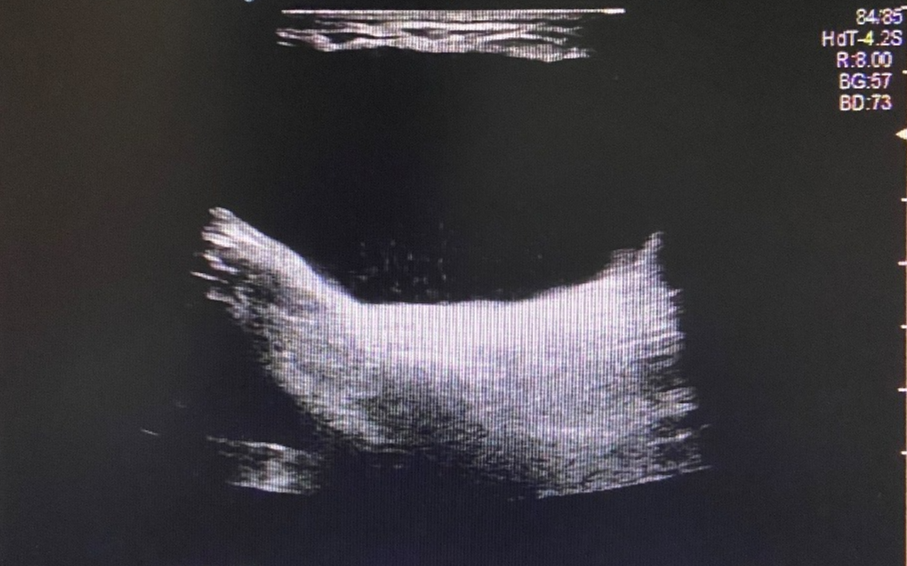

图片

图 1 左侧腹股沟区包块

超声所见

左侧腹股沟区见范围约 4.4cm×3.2cm×2.0cm 无回声区,可见少量分隔,增减腹压大小无明显变化。右侧腹股沟区未见明显异常回声。

超声提示

左侧腹股沟无回声区,子宫圆韧带囊肿?积液?

术后证实为左侧子宫圆韧带囊肿。